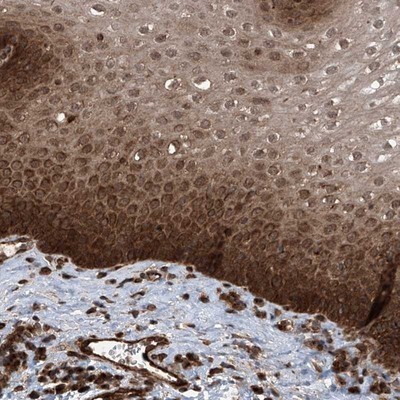

Supportive validation

- Submitted by

- Novus Biologicals (provider)

- Main image

- Experimental details

- Immunohistochemistry-Paraffin: LYSMD4 Antibody [NBP1-83511] - Staining of human esophagus shows strong cytoplasmic and nuclear positivity in squamous epithelial cells.